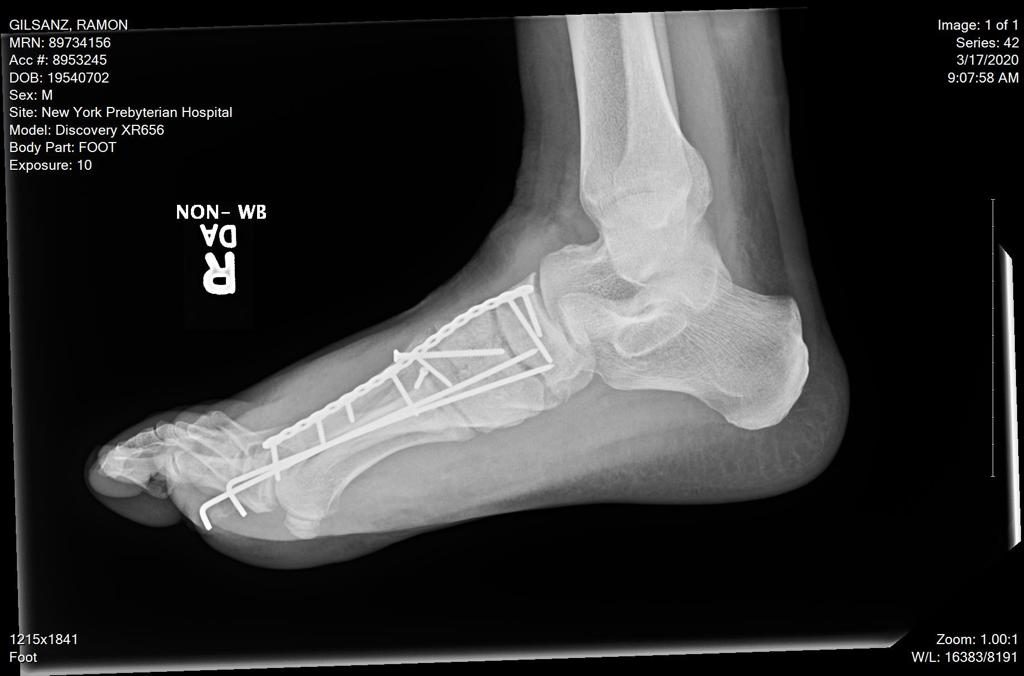

Last February I was in a devastating motorcycle accident. Four of the five bones that connect the ankle to the toes were broken, several in multiple places some of the broken bones punctured the skin in what is called an open or compound fracture. I was told by multiple doctors that I would never walk again. I made my way to Dr. Dziadosz (3 plane rides and 60 hours after the accident) with the help of family and friends. Dr. Dziadosz told me with confidence that I would walk again within the year. He was right. 11 months later I walk around 33 miles a week and I can do 8 miles in a day without a limp, and without a cane. Something I never thought would be possible again.